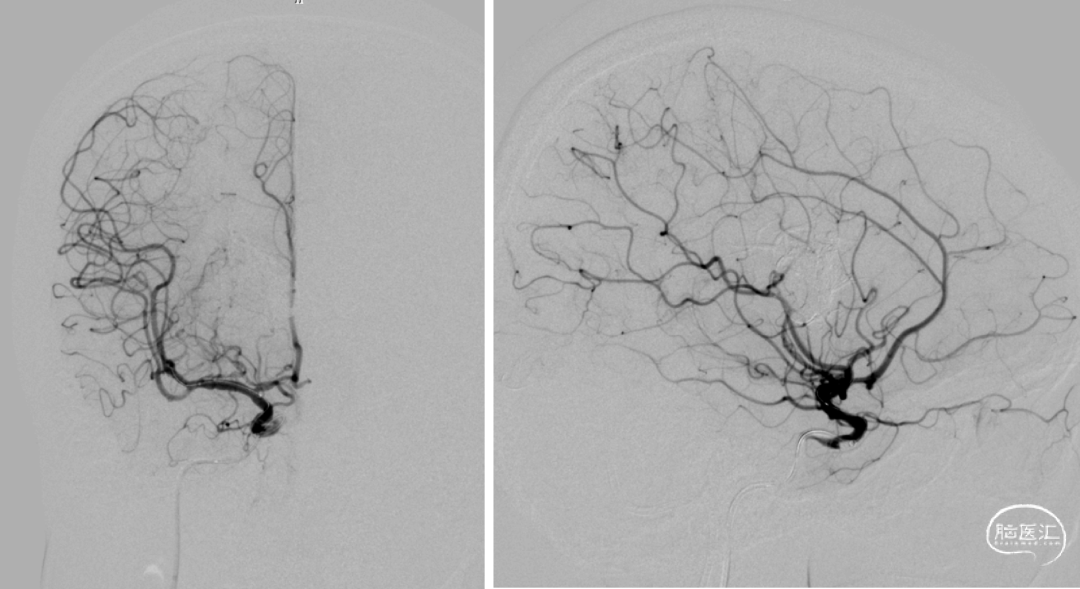

术中:即刻造影脑动静脉畸形消失。